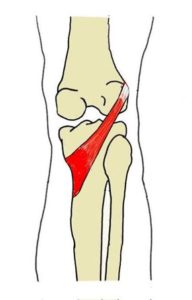

あのクリスティアーノ ロナウド選手も苦しんだ 膝関節内側靭帯損傷 Mcl損傷 とは 大阪市北浜 守口市の整骨院ならa T 長島治療院へ

内側側副靭帯損傷 カイマ接骨院